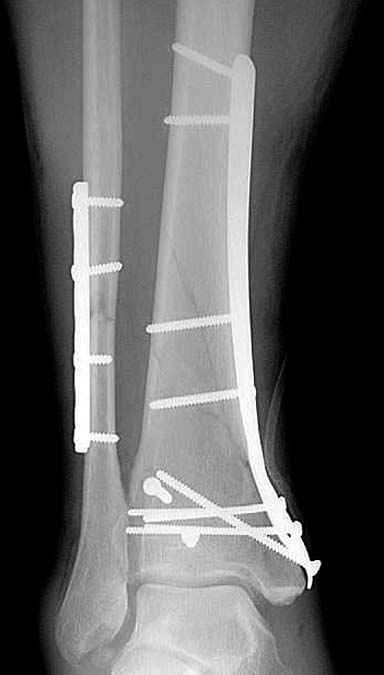

В то время метод Илизарова был на пике славы, и многие, как альтернативу пластинам, при внутри- и околосуставных переломах стали применять аппараты. Закрытая репозиция и возможности манипуляции мульти-направленными спицами в коротком отломке создавали преимущества перед другими методами.

Приход анатомических преконтурированных тонких пластин с угловой стабильностью изменил методику лечения низких переломов. Современные пластины устанавливаются из минидоступов и разделяются на правые и левые. Можно установить латерально, медиально или спереди в полиаксиальных направлениях.

Без современных материалов создать хорошую фиксацию становится трудной задачей, и этот случай характерен тем, что достигнутую идеальную репозицию испортили старомодной техникой. Исследования показали, что спонгиозные шурупы в метафизарных частях не создают механические преимущества как считали раньше. Кортикальные винты менее агрессивны и не оставляют дефекта кости после их удаления.

Низкопрофильные преконтурированные пластины с угловой стабильностью создают меньше проблем с медиальным покрытием, а толстая пластина становится раздражителем после спадения отека.

Здесь представлены несколько примеров снимков с осложнением, медиальная пластина, медиальная в комбинации с латеральной, метод Илизарова, а также сравнительные данные толщины медиальных пластин Synthes 4.4 mm, DePuy 3.2 mm.